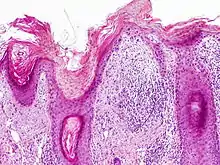

Normal skin (left) and actinic keratosis (right) with the defining characteristic of atypical basal keratinocytes that do not involve the full thickness of the epidermis.

On histologic examination, actinic keratoses usually show a collection of atypical keratinocytes with hyperpigmented or pleomorphic nuclei, extending to the basal layer of the epidermis. A "flag sign" is often described, referring to alternating areas of orthokeratosis and parakeratosis. Epidermal thickening and surrounding areas of sun-damaged skin are often seen.[39] The normal ordered maturation of the keratinocytes is disordered to varying degrees: there may be widening of the intracellular spaces, cytologic atypia such as abnormally large nuclei, and a mild chronic inflammatory infiltrate.[40]

Specific findings depend on the clinical variant and particular lesion characteristics. The seven major histopathologic variants are all characterized by atypical keratinocytic proliferation beginning in the basal layer and confined to the epidermis; they include:[39]